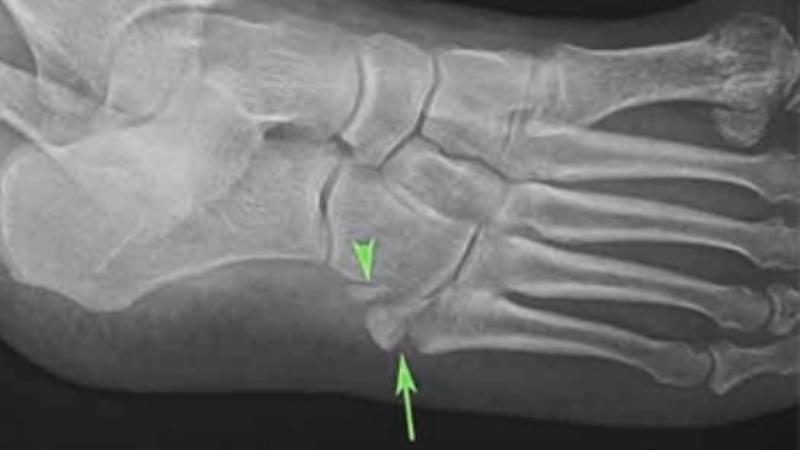

Ниже представлено изображение перелома кубовидной кости стопы: